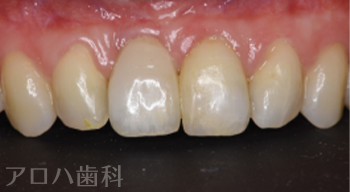

CASE02/30代女性

治療終了後3年時

| 主訴 | 右の前歯が折れた、矯正治療もしたい |

| 治療内容 | 転んで前歯を失った方です。 下の前歯もガタガタが気になるとのことで、矯正治療と並行してインプラント治療を行いました。 治療後3年間経過していますが、ほとんど骨吸収なく順調な経過をたどっています。 |

| 治療期間 | 6か月 ※矯正治療期間は別途 |

| 治療費用 | 605,000円 ※矯正治療費用は別途 |

| 費用詳細 | ・サージカルガイド 55,000円 ・GBR 110,000円 ・インプラント手術+アバットメント+上部構造 440,000円 |